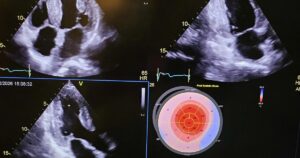

Phẫu thuật ghép tim và gan thành công cho bệnh nhân mắc bệnh hiếm

Năm 2024, bệnh nhân đến Bệnh viện Việt Pháp Hà Nội thăm khám sức khỏe [...]